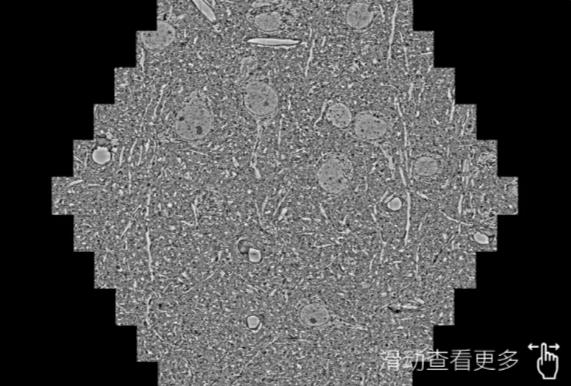

鼠脑切片。左图使用常德蔡司常德扫描电镜MultiSEM706对165μmx143pm面积区域成像,耗时仅需1.5秒。右图为鼠脑切片中30μm区域放大效果。样品由芝加哥大学B.Kasthuri提供。